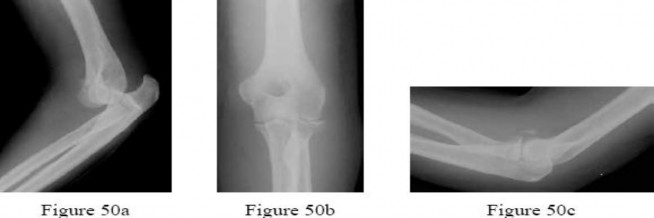

Figure 50cFigure 50a is the radiograph of a 25-year-old man who fell off his bike, landed on his outstretched elbow, and sustained a closed fracture-dislocation of the elbow. After urgent closed reduction, he has no neurovascular compromise. Postreduction radiographs are shown in Figures 50b and 50c. What is the most appropriate management?

What is the most common complication following surgery for a “terrible triad” elbow fracture-dislocation?